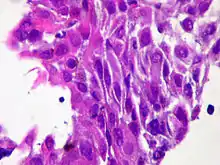

| Micrograph of squamous-cell carcinoma (H&E stain) | |

Squamous epithelial cells are not found in normal thyroid, thus the origin of SCT is not clear. However, it might be a derived from the embryonic remnants such as thyroglossal duct or branchial clefts. Often SCT is diagnosed in one of the thyroid lobes, but not in the pyramidal lobe. Another possible way of SCT development can be through the squamous metaplasia of cells. However, that theory is also controversial, since the Hashimoto's thyroiditis and chronic lymphocytic thyroiditis (neoplasms to be showed squamous metaplasia) are not associated with SCT. Primary STC is usually diagnosed in both lobes of thyroid gland. The histopathology of STC shows a squamous differentiation of tumor cells.